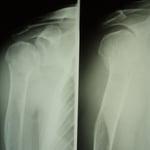

●右鎖骨骨折

当患者さんは手術療法に強く抵抗があり当院での保存療法を選択されました。

骨折部位の短縮転移があたので整復操作が必須になります。運よく短縮転移が矯正されたので保存療法で経過をみました。暑い時期だったので来院の度に固定を外し体を清拭して施術後、新しい下着の上から再度固定をする運びになりました。

骨折部位には超音波、患部以外の所は関節運動、経過を見て軽いマッサージを開始。固定も少しずつ簡易な物へ変更し二カ月後には三角巾のみ、三ヵ月経過すると肩関節の挙上もできるようになりました。

経過良好で完治しました。

左のレントゲンは短縮転位 (受傷時) 右は整復操作をして骨片が重なり合っている状態

整復後包帯と装具で固定。当初は週に2、3回来院してもらいその都度固定は取り外し、体を洗いました。

通常整形外科では取り外しも清拭もしないので暑い時期は患者様には試練です。ストレスは悪影響をもたらします。

局所には超音波治療を施し浮腫みのある指、肘はマサージににより軽減に努めました。6週ほど固定しましたが、各週ごとに固定を楽にしていくのでかなりストレスを軽減できたと思います。3か月目には肩を挙上できるまでになり、筋力強化運動により完治しました。